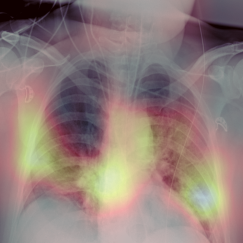

Early screening of patients is a critical issue in order to assess immediate and fast responses against the spread of COVID-19. The use of nasopharyngeal swabs has been considered the most viable approach; however, the result is not immediate or, in the case of fast exams, sufficiently accurate. Using Chest X-Ray (CXR) imaging for early screening potentially provides faster and more accurate response; however, diagnosing COVID from CXRs is hard and we should rely on deep learning support, whose decision process is, on the other hand, "black-boxed" and, for such reason, untrustworthy. We propose an explainable two-step diagnostic approach, where we first detect known pathologies (anomalies) in the lungs, on top of which we diagnose the illness. Our approach achieves promising performance in COVID detection, compatible with expert human radiologists. All of our experiments have been carried out bearing in mind that, especially for clinical applications, explainability plays a major role for building trust in machine learning algorithms.